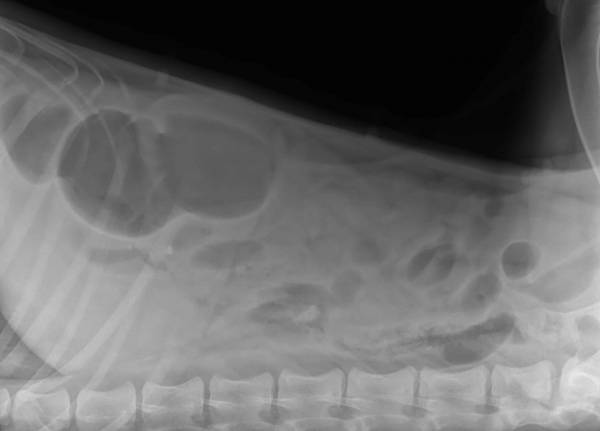

The one x-ray that appears to be a top view shows an obvious enlargement on the ride side. It appears to me that there is some foreign matter going on. Stomach flip as Nan said...I can see that too.

I see very beautiful croup and super chest ![]()

3 vets at first hospital saw these, and the 1 vet I sent them to saw them. All saw obstructive pattern, albeit unclear as far as the nature of the obstruction. I'm extremely careful about what the dogs have access to, but Eden is a trouble-maker. She loves to grab something out of the hamper on her way out the backdoor through the laundry room. I find my son's clothes outside regularly- she's just sneaky enough to turn her head so we don't notice what she's got in her mouth. If any of mine are going to eat something stupid, it's Eden.

Argh! I didn't see Ibrahim's or Susie's post. Susie, they didn't use any contrast. I am not sure why. Ibrahim, what's funny, is that these are a better view of her hips than he OFA x-rays were! LOL! THOSE were inexcusably horrendous! I should send this one to the vet who shot her OFAs and say "an x-ray for possible obstruction was positioned 100x better than your xray TRYING to show her hips."